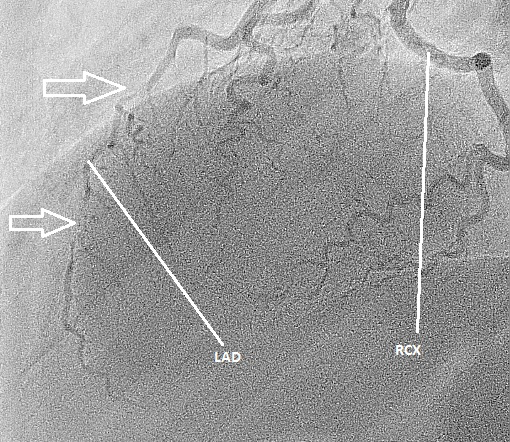

Figuur 3: angiografie beeld van de linkerkransslagader met de buisstand in links craniale projectie. De witte pijlen geven aan waar er een dissectie is opgetreden van het bloedvat (de LAD). RCX= ramus circumflexus.